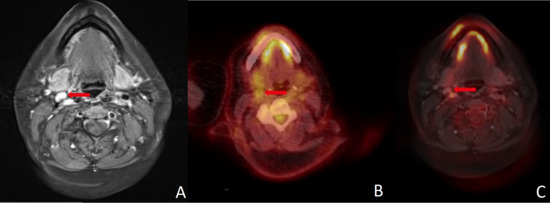

Patients with malignancy confirmed by histology were assessed as false negative in five (13.5%) cases by MRI, in five (13.5%) cases by PET/CT and in five (13.5%) cases by PET/MRI (see Figure 2). In one (2.7%) case, both MRI and PET/CT were false negative and PET/MRI identified a suspicious lymph node. Conversely, one (2.7%) patient was diagnosed false negative in PET/MRI, while MRI and PET/CT detected a suspicious finding (see Figure 2).

Figure 2.

(A) MRI yielded a false negative finding, whereas (B) PET/CT, (C) PET/MRI and histopathology all confirmed malignancy. The FDG uptake combined with high soft-tissue contrast in (C) PET/MRI can simplify image interpretation and help guide surgery. Red arrows point to the region of interest in all three imaging modalities.

A major limitation of nearly all imaging methods is the detection of small LNMs. Yamazaki et al. found true positive LNMs in PET/CT to have a mean diameter of 13.4 mm, whereas false negatives had a mean diameter of only 3.1 mm [32]. Accordingly, they described the diagnostic accuracy to be poor in nodes smaller than 10 mm [32]. The challenge in this respect is that a large proportion of LNMs are smaller than this margin [33]. Since MRI attempts to overcome this limitation using DWI and DCE, it appears promising to combine PET with DCE-MRI. However, our data did not provide evidence for improved assessment of small nodes, although in one case FDG-PET could reveal LNM in a positive neck that was not registered in MRI (see Figure 2). Interestingly, elevated risk of LNM in histology (T classification ≥ 3, lymphatic invasion, grading ≥ 3 and/or p16 positivity) seems to be associated with a higher risk of divergent results in different imaging modalities, since only one of seven patients with divergent imaging results did not have elevated risk in histology.